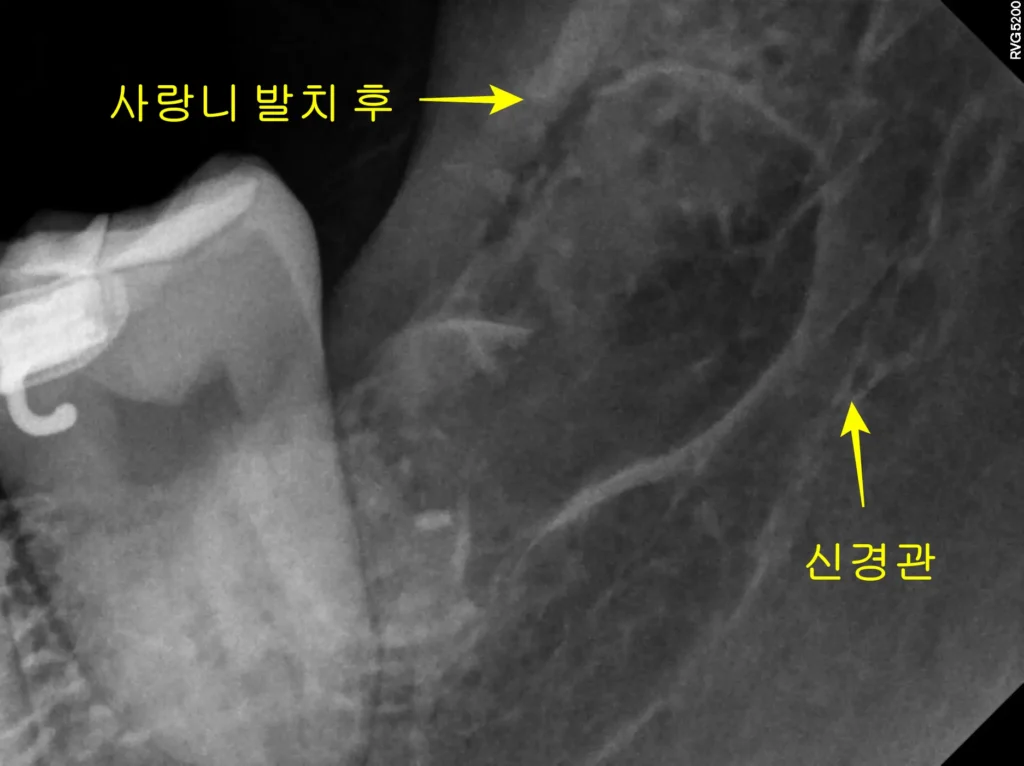

이번에 내원하신 환자분도 타 치과에서 발치가 어렵다는 소견을 듣고 오셨습니다. 사랑니가 신경과 가깝고 뿌리가 휘어진 고난도 케이스였습니다.

STEP 1 정밀 진단 및 계획 수립 먼저 파노라마와 3D CT를 분석합니다. 하치조 신경관과 사랑니 뿌리의 거리를 파악합니다. 이번 경우는 뿌리가 신경 쪽으로 휘어 있어 주의가 필요했습니다.